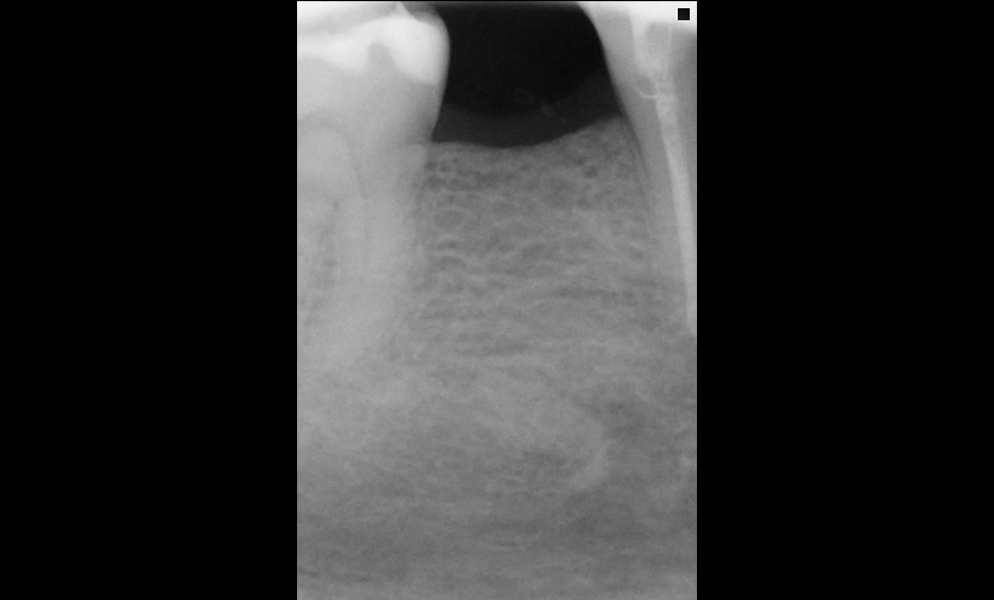

| Before | After |

![]() |

| Single posterior tooth missing space restored with a short dental implant (Bicon, USA) | |